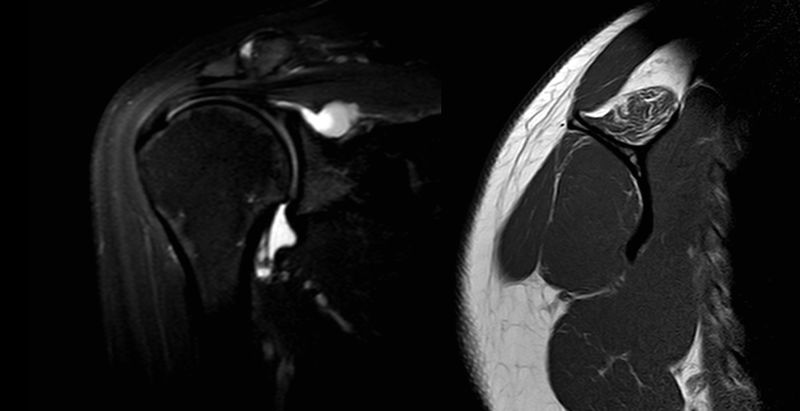

Left: MRA coronal view with T2 sequences revealing a large spinoglenoid cyst. Right: MRI sagittal view of the same patient with T1 sequences of a fatty infiltrated supraspinatus.